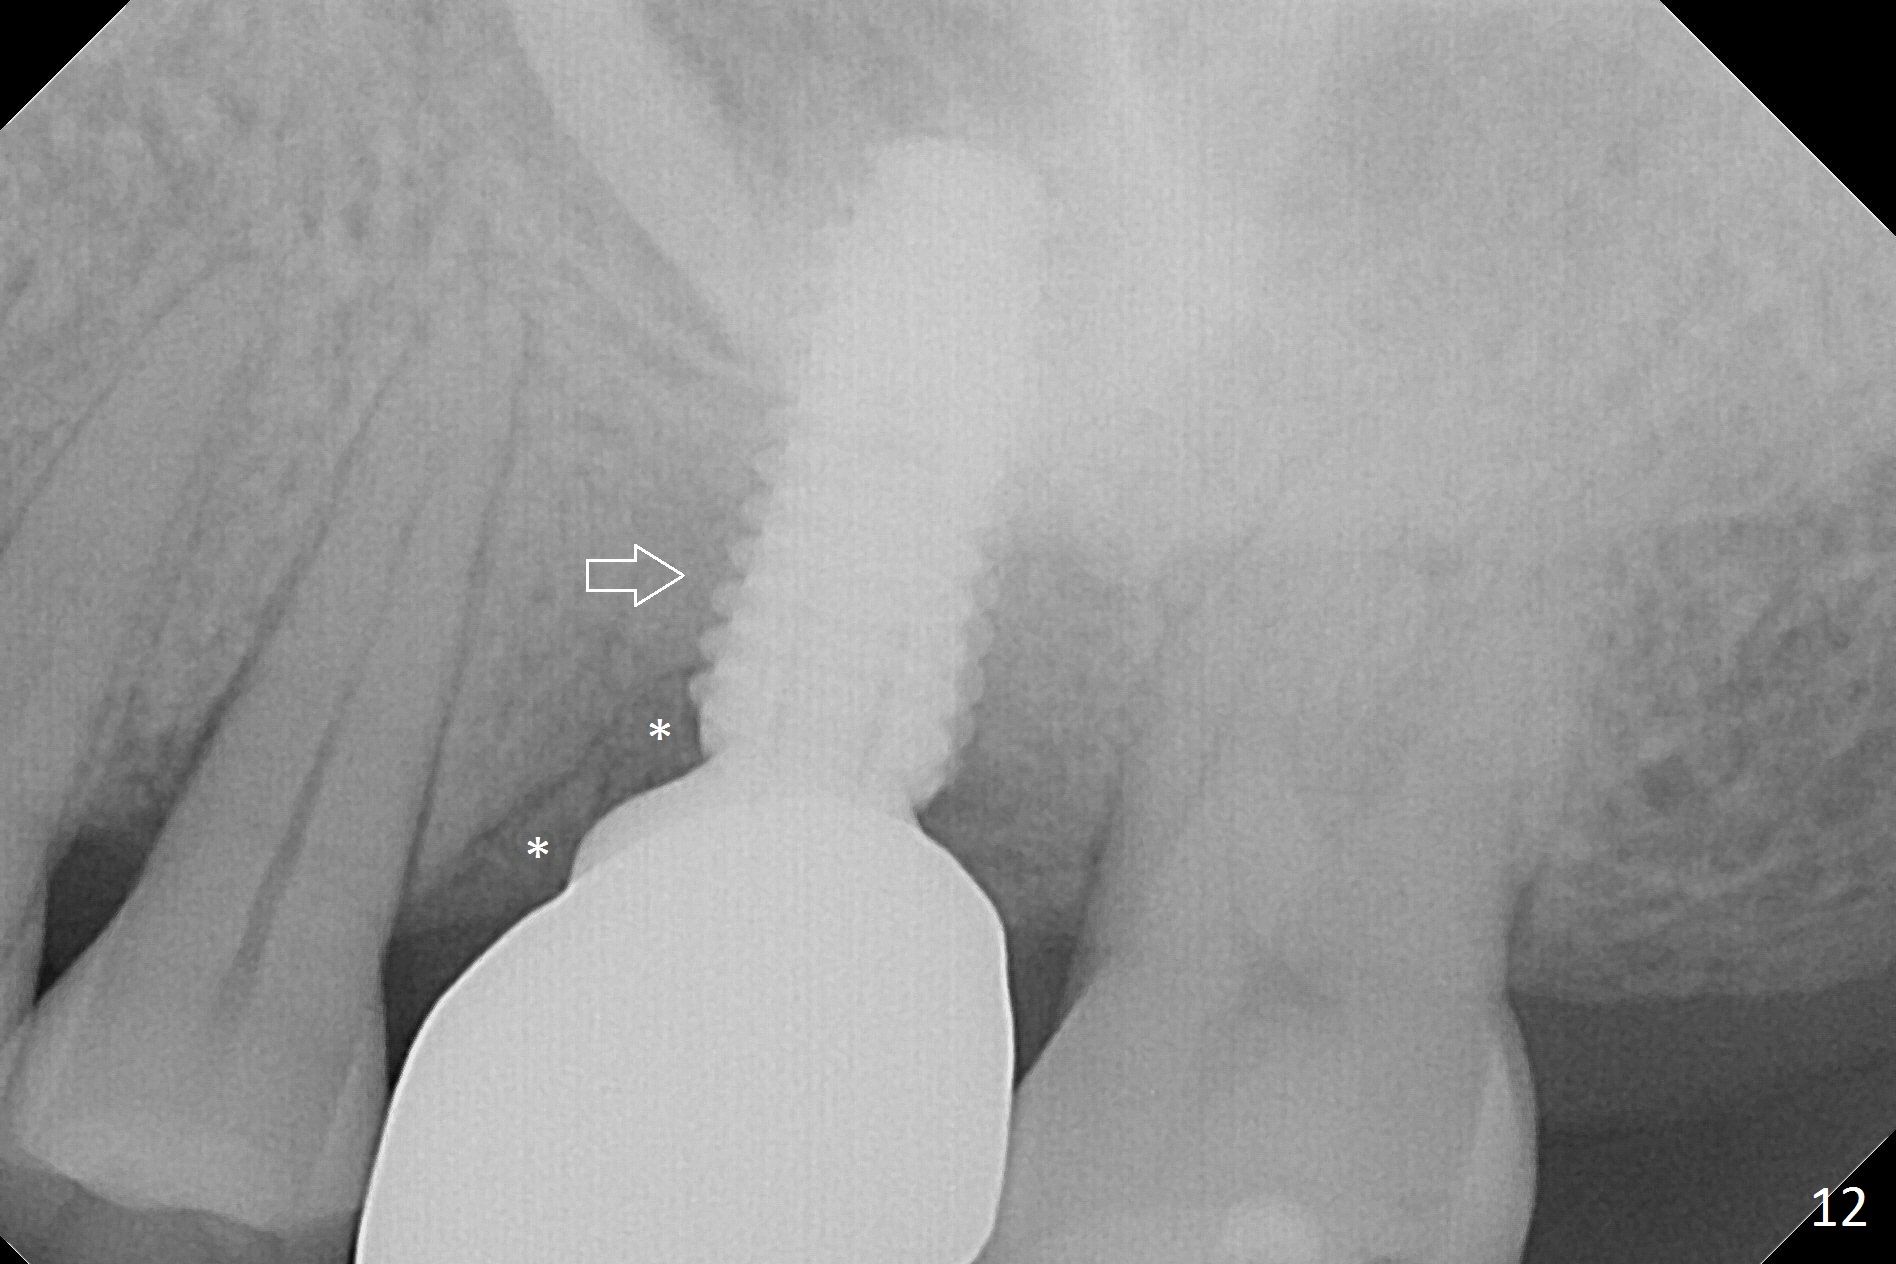

The patient experiences palatal gingival tenderness 5 months post cementation, probably due to loose proximal contacts and excessive use of floss. PA shows new normal bone next to the upper threads (Fig.12 arrow), while new less dense attached to the most coronal threads (*). BWs (Fig.13,14) shows that new bone has grown into the area between the most coronal 2 threads (arrows). When the crown and abutment are removed, the gingiva looks normal except minor laceration buccally. A 7.5x4 mm healing abutment is placed. If the infection resolves, pick up impression will be taken to add porcelain to the proximal surfaces to prevent food impaction.